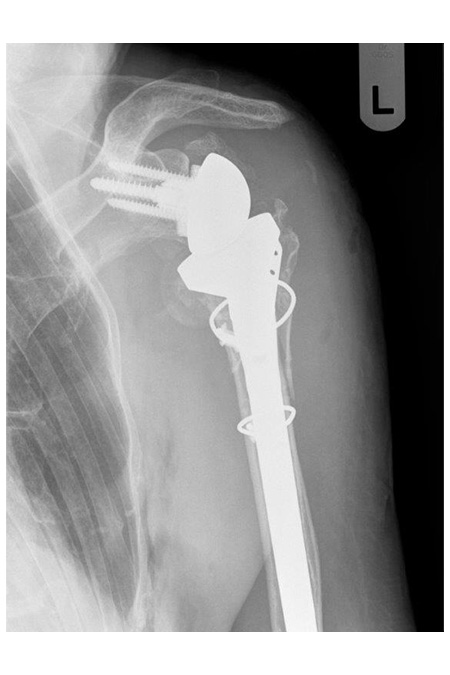

79 Jährige Patientin mit Oberarmkopffraktur und Plattenosteosynthese auswärtig versorgt stellt sich hier mit einem völligen Schultergelenksfunktionsverlust und Zusammenbruch des Oberarmknochens sowie Verschiebung bei liegender winkelstabiler Platte vor.

Es wurde die Platte entfernt und das Gelenk mit einer zementfreien Inversen Schultergelenksprothese nach Lösung der Verklebungen und Neufixierung der Sehnen wieder aufgebaut. 3,5 Monate nach operativer Versorgung sind die Sehnenansätze gut eingeheilt und eine ansprechende nahezu schmerzfreie Funktion erreicht.